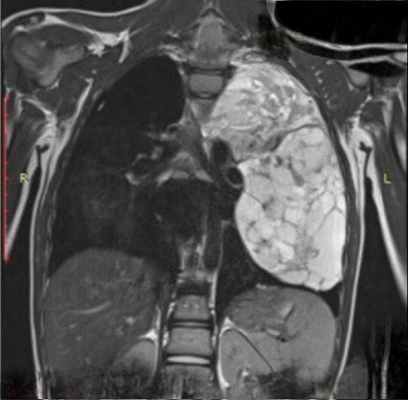

Рентгенологическое исследование: срединная тень почти на всем своем протяжении расширена в обе стороны за счет патологического затемнения, занимающего большую часть переднего средостения. Это интенсивное, неоднородное затемнение имеет дольчатую форму с бугристыми четкими контурами, расположенными местами (справа) в виде «кулис». На жестком снимке с передержкой и на томограммах более отчетливо выявляется дольчатый характер патологического образования и узлы, расположенные на различной глубине, видны также неизмененные трахея и главные бронхи. Пищевод не изменен.

Очаговых и инфильтративных изменений в легких не определяется. Куполы диафрагмы подвижны, синусы свободны. Корни легких, сердце и аорта не определяются из-за наложения на них описанного затемнения.

Полученные клинические и рентгенологические данные свидетельствовали о быстро развивающемся злокачественном процессе в переднем средостении, видимо, с метастазированием в надключичные лимфатические узлы. Таким образом, первые два этапа дифференциальной диагностики не представляли никаких затруднений. Но необходимо было определить гистологическую сущность этой опухоли. Практически в первую очередь приходилось думать о трех заболеваниях: лимфогранулематозе, лимфосаркоме и злокачественной опухоли вилочковой железы.